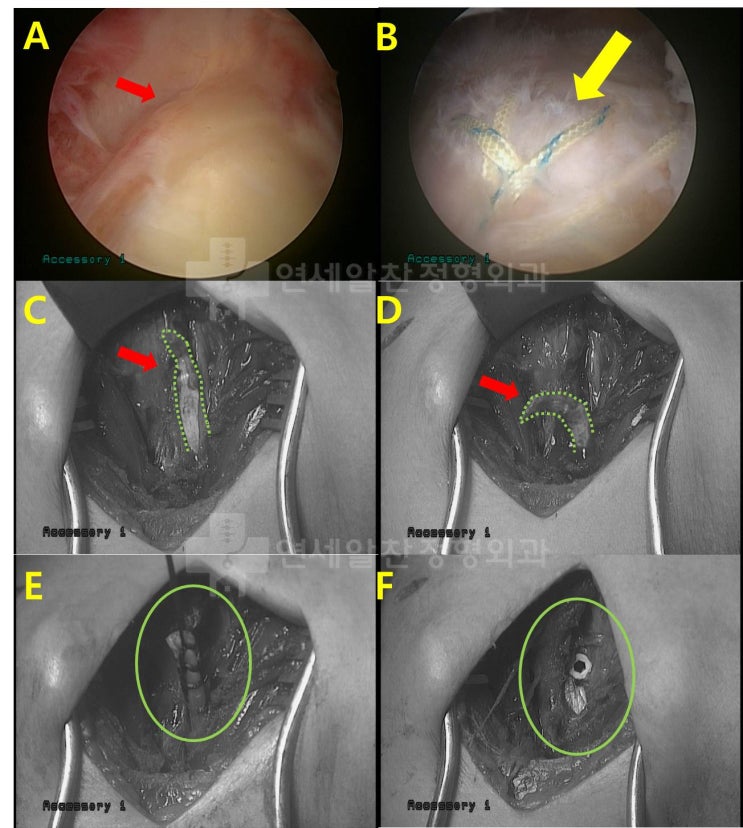

어깨 회전근개 파열 : 보다 단단하게 봉합하는 이열봉합법

안녕하세요. 정형외과 전문의 이동규 입니다. 오늘은 회전근개 파열에서 관절경 수술시 더 단단하게 봉합하...

회전근개파열 에서 이열교량형 봉합법 에 대한 고찰

회전근개 파열 을 수술할 경우 봉합법에 대한 문의를 하는 경우가 종종 있다. 회전근개파열 이 있는 경우 ...